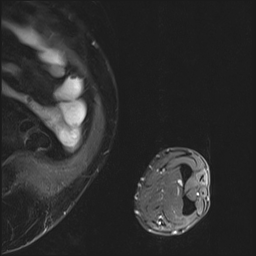

5.3.1 Coherence Score of Annotations

We chose the Fusion_Gate method for our application-grounded evaluation because it achieved the highest scores, albeit modest, in our functionally-grounded evaluation. Figure 7 presents all five distal myopathy cases side by side with their reference masks and the corresponding Fusion_Gate saliency maps, providing a direct visual comparison of true pathology versus model-identified regions. After converting each HCP’s annotations into binary masks, we computed the coherence between those masks and the Fusion_Gate saliency maps (Table 7). The large spread in RMA and RRA values demonstrates that even minor discrepancies in the ground truth mask can dramatically alter coherence scores, emphasizing the critical need for highly accurate, consensus ground truth annotations when using coherence as an interpretability metric. We then assessed each HCP’s overall annotation accuracy by RMA¯\overline{\mathrm{RMA}}over¯ start_ARG roman_RMA end_ARG and RRA¯\overline{\mathrm{RRA}}over¯ start_ARG roman_RRA end_ARG against the reference masks (first column of Table 8). RMA¯\overline{\mathrm{RMA}}over¯ start_ARG roman_RMA end_ARG indicates that HCPs reliably identify the general signal alteration regions, but their consistently lower RRA¯\overline{\mathrm{RRA}}over¯ start_ARG roman_RRA end_ARG confirms they lack the fine-grained precision of the expert in isolating the most critical subregions. Notably, when we compare these human baselines to the Fusion_Gate’s mean coherence scores (Table 5), the method’s RRA¯\overline{\mathrm{RRA}}over¯ start_ARG roman_RRA end_ARG surpasses that of all but two HCPs. In other words, the attention mechanism could faithfully highlights the single most important pixel than most individual annotators. Lastly, the comparatively low RMA¯\overline{\mathrm{RMA}}over¯ start_ARG roman_RMA end_ARG and RRA¯\overline{\mathrm{RRA}}over¯ start_ARG roman_RRA end_ARG values in the second column of Table 8, which quantify how well the Fusion_Gate saliency maps align with each HCP’s own mask, reveal that even our best interpretability method still falls short of expert-level delineation. In other words, although attention-based saliency can highlight broadly relevant regions, it does not yet match the clinical precision of HCPs’ annotators. This gap underscores that, despite promising advances, more work is needed before automated explanations can achieve the same fidelity as experienced radiologists.

Refer to caption

(a) Image 1

(b) Ground truth Mask 1

(c) Saliency Map 1

(d) Image 2

(e) Ground truth Mask 2

(f) Saliency Map 2

(g) Image 3

(h) Ground truth Mask 3

(i) Saliency Map 3

(j) Image 4

(k) Ground truth Mask 4

(l) Saliency Map 4

(m) Image 5

(n) Ground truth Mask 5

(o) Saliency Map 5

Figure 7: Image instances of the distal myopathy dataset with their corresponding reference masks and saliency maps.